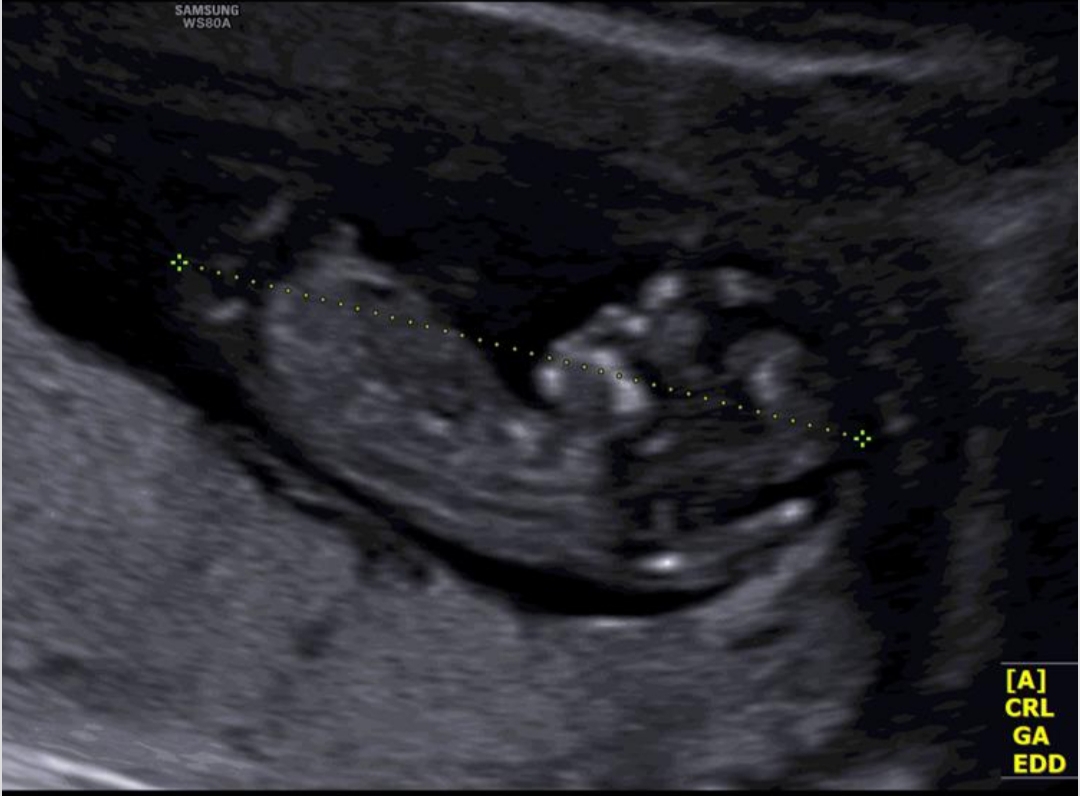

حس ششم نیستم ولی تا دیدمش حس کردم پسر

نمیدونم منم حس میکنم پسره

فقط 33 هفته و 6 روز به تولد باقی مونده !